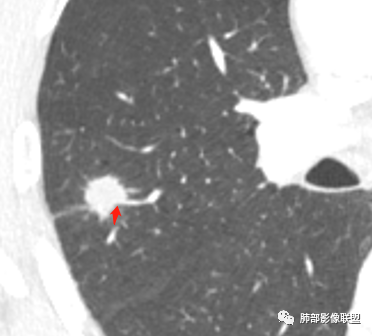

影像学改变:

1.右肺上叶后段类圆形结节影,密度不均,有坏死空洞,坏死比较彻底,内外壁都较清楚。

2.病灶有浅切迹,没有深分叶,毛刺大多细长且柔软。

3.可见棘状突起及胸膜牵拉,但未见胸膜凹陷。

什么意思?结节影有牵拉的动作,但似乎“出工不出力”,收缩力羸弱!

4.病灶轻到中度强化。病灶内血管走行较完好,病灶旁血管局部显示粗大。

5.支气管关系不确定。

6.灶周见小结节影(卫星灶),边界不甚清晰。